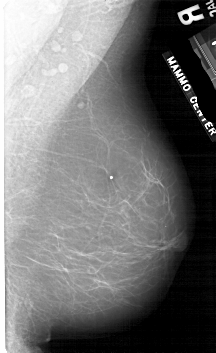

ics_version 1.0 filename A-1754-1 DATE_OF_STUDY 9 5 1996 PATIENT_AGE 59 FILM FILM_TYPE REGULAR DENSITY 1 DATE_DIGITIZED 16 3 1999 DIGITIZER HOWTEK 43.5 SEQUENCE LEFT_CC LINES 5491 PIXELS_PER_LINE 3556 BITS_PER_PIXEL 12 RESOLUTION 43.5 OVERLAY LEFT_MLO LINES 5341 PIXELS_PER_LINE 3361 BITS_PER_PIXEL 12 RESOLUTION 43.5 OVERLAY RIGHT_CC LINES 4996 PIXELS_PER_LINE 2956 BITS_PER_PIXEL 12 RESOLUTION 43.5 NON_OVERLAY RIGHT_MLO LINES 5281 PIXELS_PER_LINE 3226 BITS_PER_PIXEL 12 RESOLUTION 43.5 NON_OVERLAY |